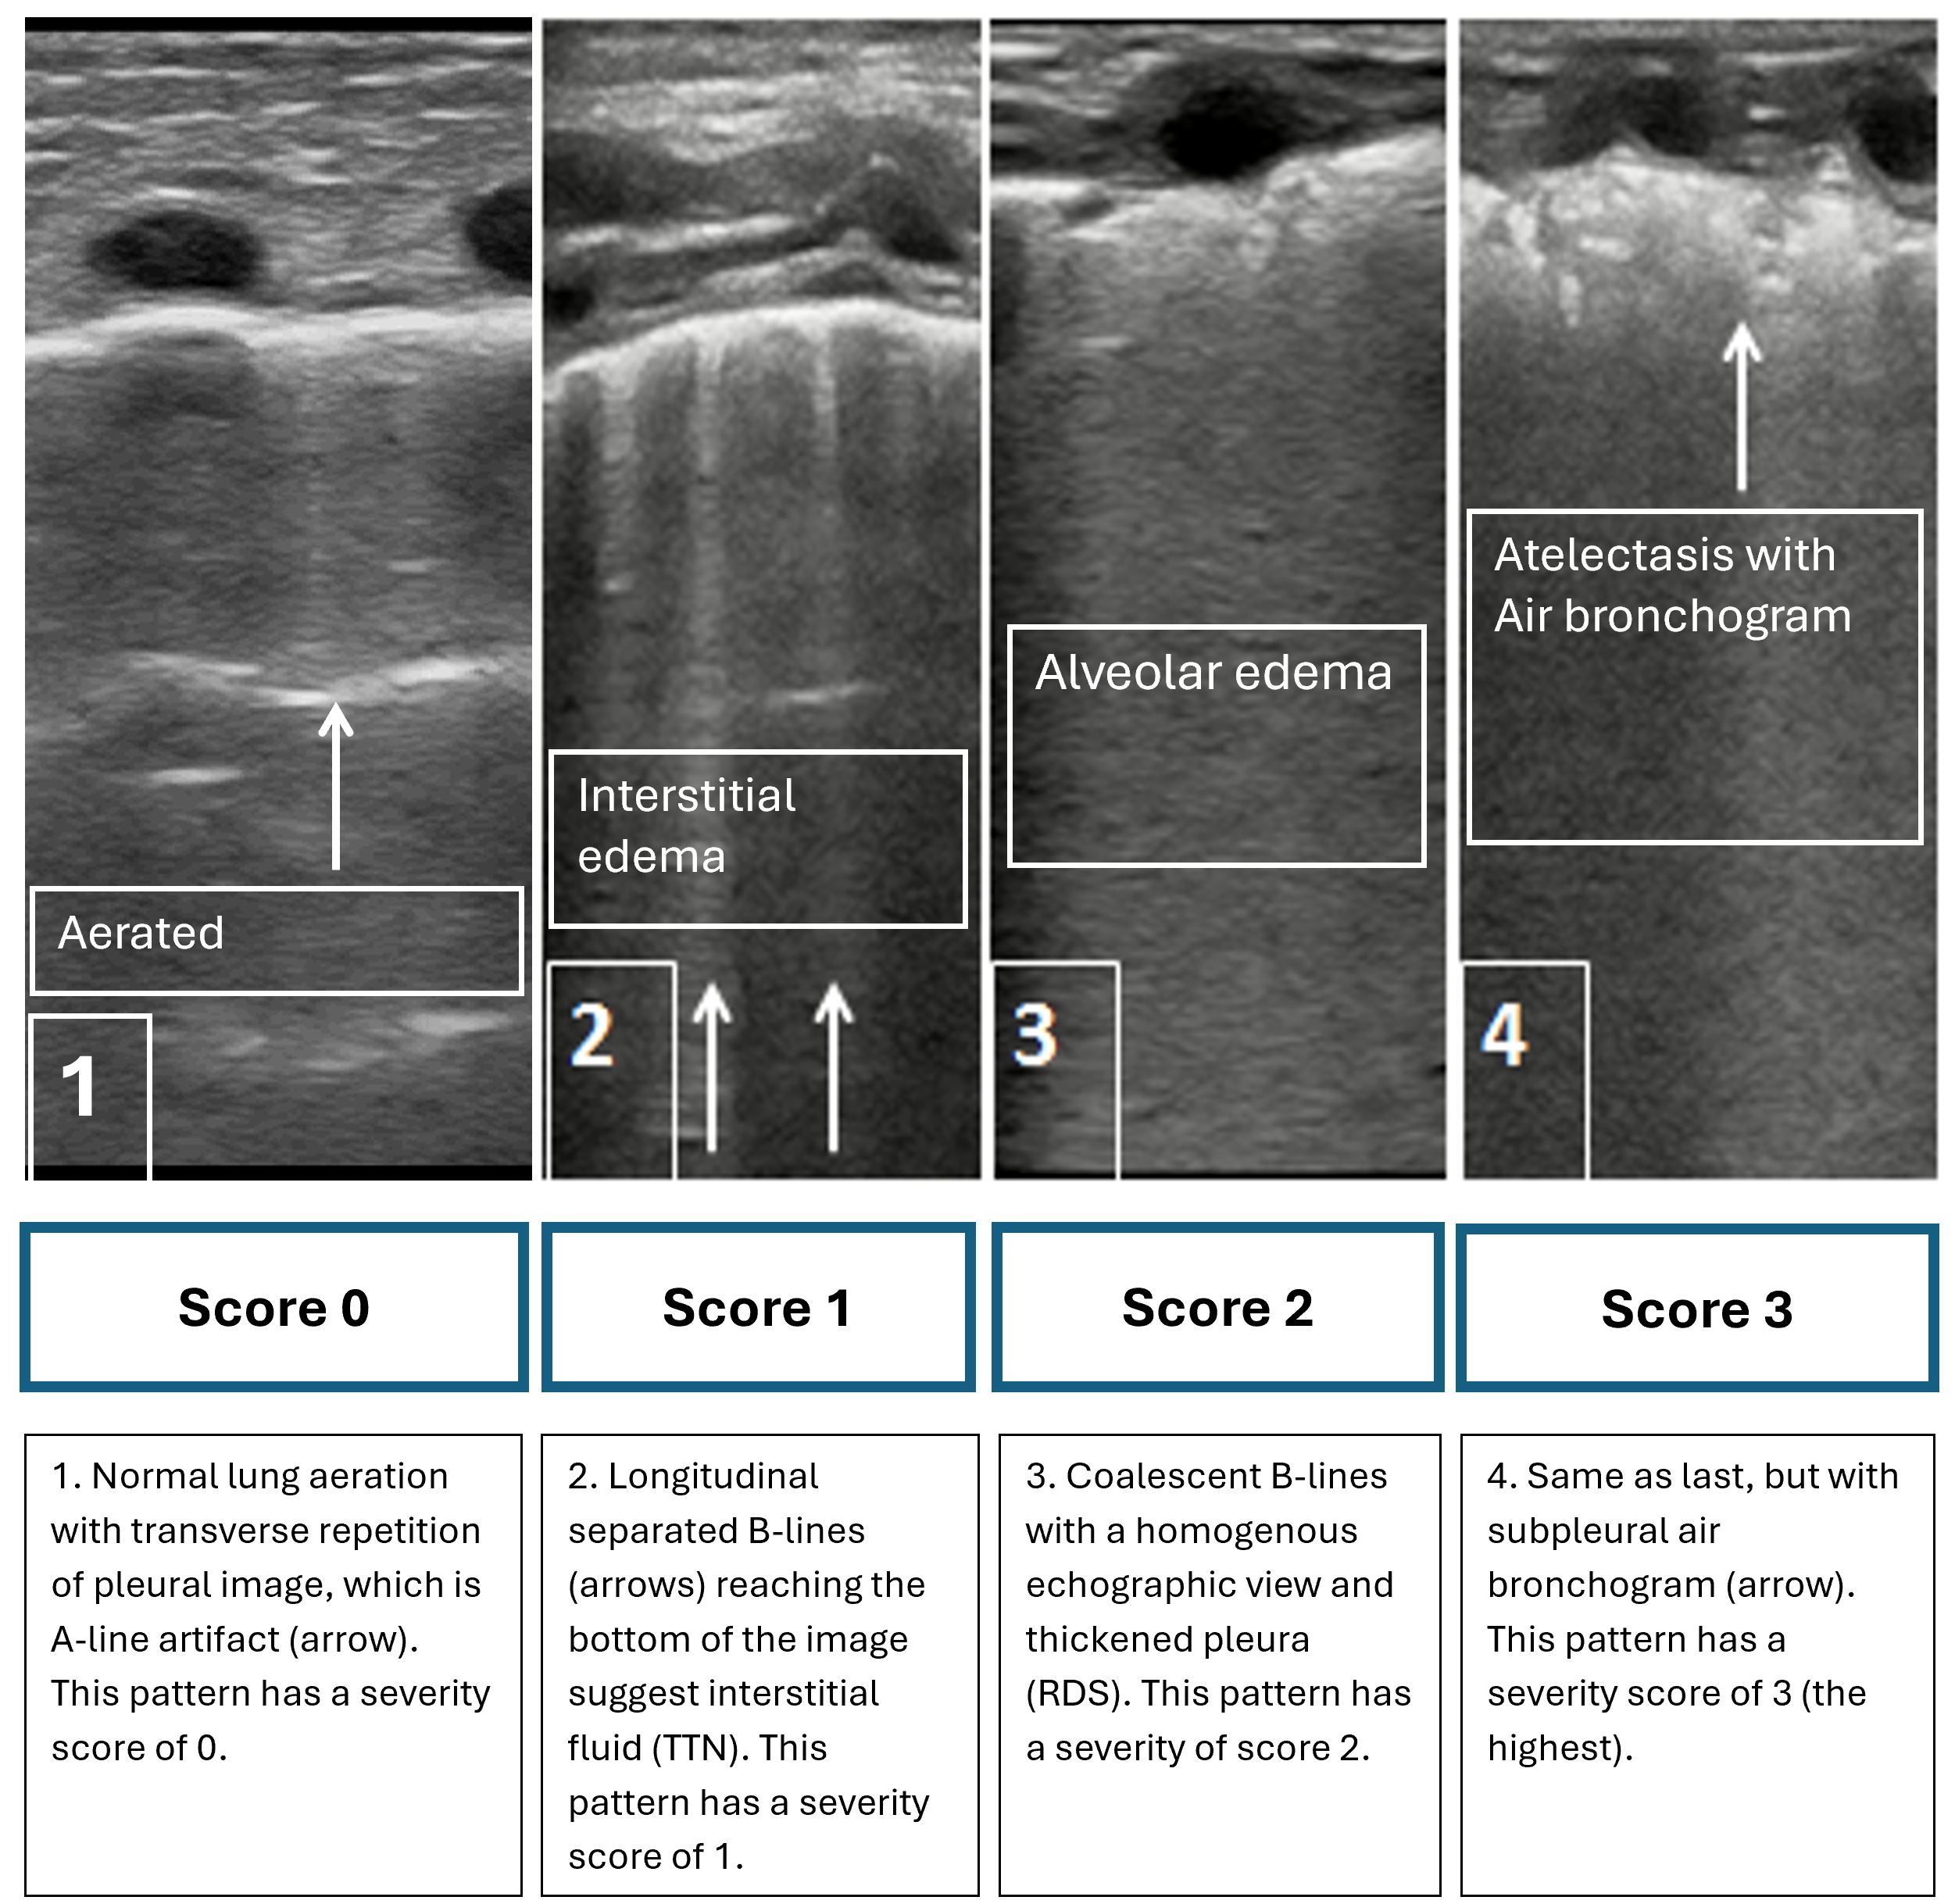

Lung POCUS is usually performed with the patient in the supine position. While any probe can be used with image depth and grain modified to demonstrate patterns, a linear probe is often preferred for clarity in practice. Four patterns of lung findings contribute to an overall severity score, with values ranging from a low of 0 to a high of 3 for each zone. Because there are three lung zones per side, scoring can range from 0 to a maximum of 18.

Figure 1 shows typical patterns and suggests interventions for common conditions in the neonate. Figure 2 from the AAP’s POCUS statement shows the lung POCUS scores and predicts responsiveness to therapeutic interventions in infants with hypoxemia. Figure 3 from the AAP’s POCUS statement describes a lung POCUS interpretation algorithm in different neonatal pulmonary conditions[11][12].

Figure 1. Four typical patterns of lung ultrasonography

RDS Respiratory distress syndrome, TTN Transient tachypnea of the newborn